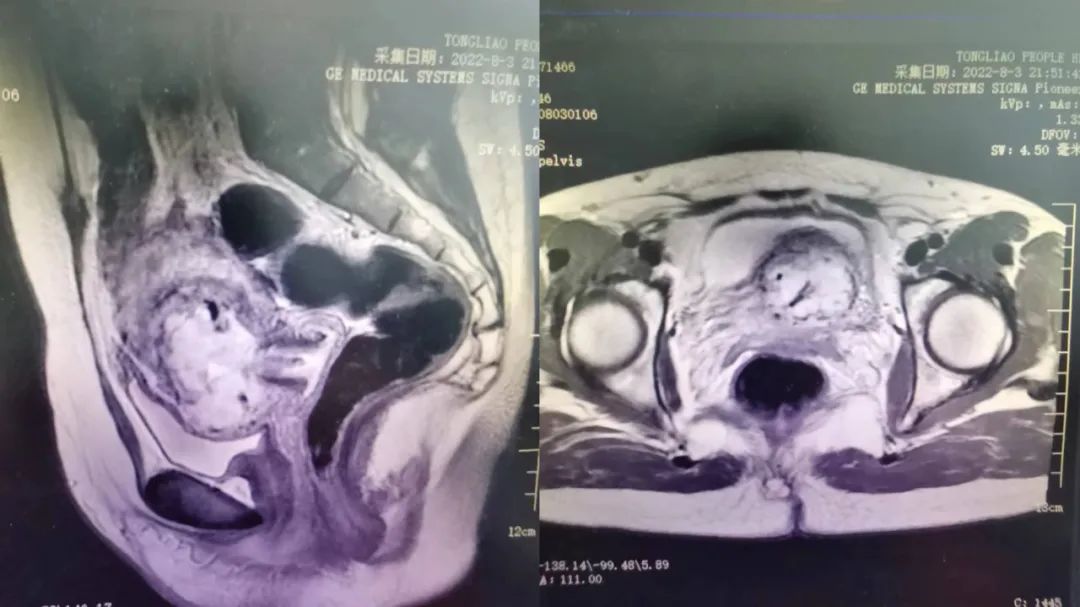

患者女性,38岁,因“停经58天,发现宫腔内囊实混合回声团块1天”入院,既往2次剖宫产史。入院后完善相关检查,人绒毛膜促性腺激素77150.00mIU/mL,盆腔MRI提示:考虑瘢痕妊娠合并胎盘植入(累及膀胱不能除外),子宫附件彩超提示:宫腔内囊实混合回声团块-不除外瘢痕妊娠,请结合血HCG。通过术前充分评估和全科集体讨论,其大出血及膀胱损伤风险高。在与患者及患者家属充分沟通后,决定先为患者施行局麻下“经皮穿刺插管超选择性子宫动脉造影、子宫动脉栓塞术(甲氨蝶呤子宫动脉内注射后明胶海绵颗粒栓塞)”术,术后复查人绒毛膜促性腺激素明显下降,复查超声提示局部血流信号明显减少。再次术前充分评估和全科集体讨论,决定行腹腔镜下Ⅲ型子宫瘢痕妊娠病灶切除术,手术成功完成,术中出血约30ml,既避免大出血、保留子宫,又修复了子宫下段,得到患者及家属的高度肯定。